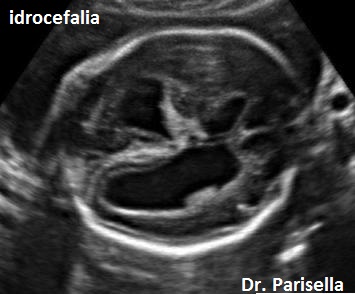

- il tipo I caratterizzata da placentomegalia ad aspetto multicistico, normosviluppo fetale e set cromosomico aggiunto di origine paterna (la dispermia è la causa più frequente di triploidia), micrognazia, anomalie del SNC (idrocefalia), cardiopatie, igroma cistico, oligoamnios.

- il tipo II caratterizzata da una placenta piccola, IUGR, set cromosomico aggiunto di origine materna (diginia), micrognazia, anomalie del SNC (idrocefalia), cardiopatie, igroma cistico, oligoamnios.